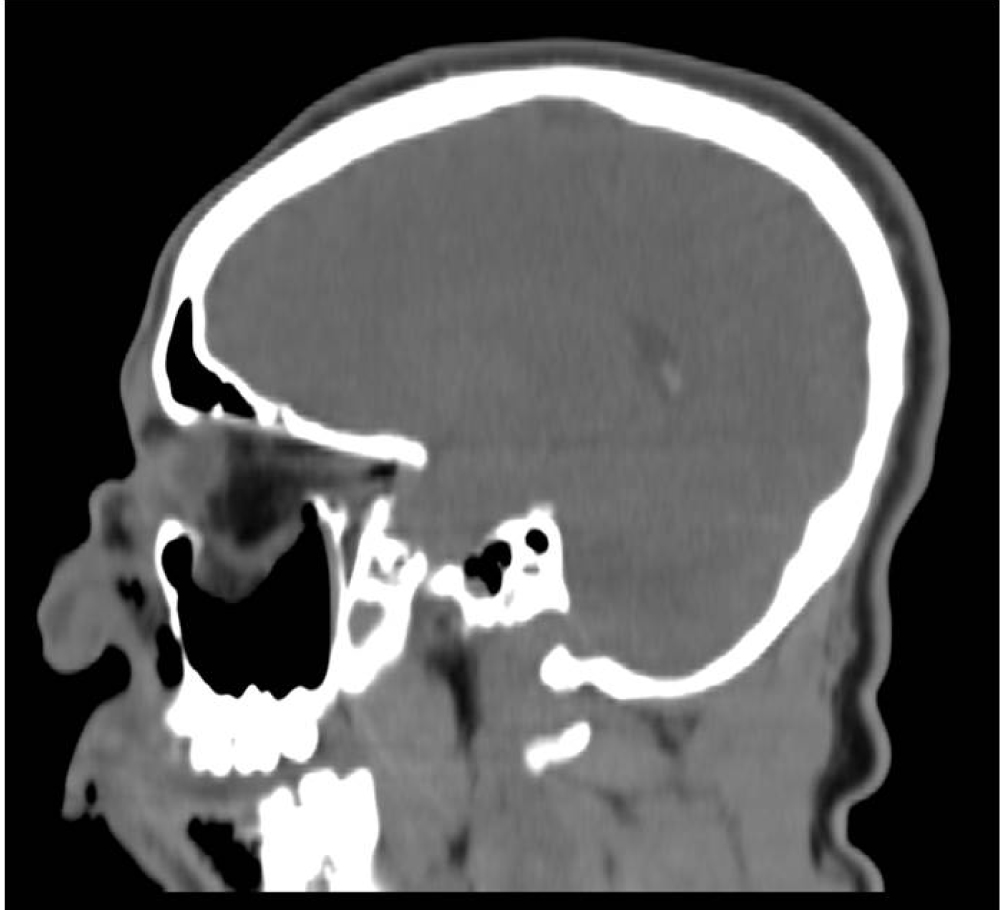

A 25-year-old man was admitted to the emergency room with multi trauma injuries after falling from a second-floor balcony into his neighbor's garden. On arrival, the patient was sedated and placed under artificial respiration. On physical examination, the only external evidence of injury was a 1.5 cm wooden foreign body protruding from the upper lip (Figure 1). Closer examination revealed the foreign body inside the cheek without penetrating the oral cavity. Computed tomography (CT) of the head and face were performed. The images depicted a well formed, radiolucent area with a density similar to that of air in the right orbit. This was later identified as a foreign body penetrating the right orbit in an axial plane from inferior to superior direction. It deflected the globe and penetrated the orbital apex towards the middle cranial fossa to the point of touching but not penetrating the dura mater (Figure 2). A fracture in the floor of the right orbit without the involvement of the lower orbital rim was revealed (Figure 3). Herniation of the inferior Rectus muscle and fat from the orbit into the right maxillary sinus cavity were present (Figure 4). Ocular examination showed no injuries to the globe. The patient received tetanus toxoid and prophylactic intravenous wide spectrum antibiotics. The patient underwent an emergency operation, in the presence of an ophthalmologist and a neurosurgeon. The approach was extra-oral with the aim of exploring and removing the foreign body. The intra-orbital foreign body proved to be a 9 cm bamboo stick (Figure 5). The bamboo stick was meticulously removed. There was no leakage of cerebrospinal fluid (CSF) and no brain tissue was found during exploration examination of the foreign body after its removal. Immediate postoperatively, the patient was transferred to the intensive care. Follow up CT scan demonstrated intact right globe, optic nerve and dura mater. There were no radiolucent findings suggesting that no foreign body remnants were present.

Figure 2: (A, B, C) 3D CT scan demonstrating a foreign body mimicking air in the orbit, deflected the globe and penetrated the orbital apex towards the middle cranial fossa to the point of touching but not penetrating the dura mater. View Figure 2